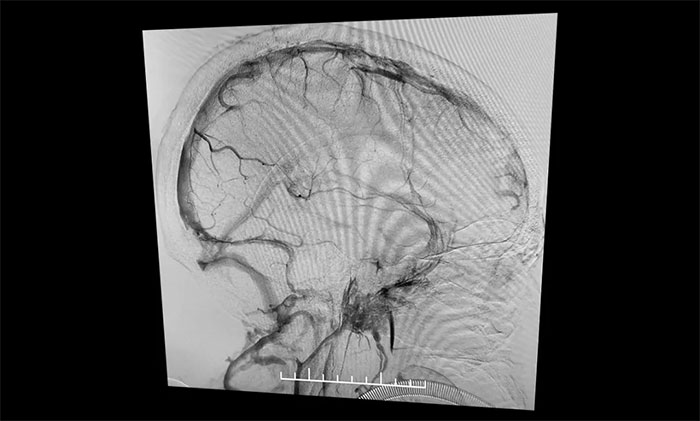

在麻醉科团队及导管室介入团队的密切配合和监护下,4A脑血管病一科主任席刚明教授、4A脑血管病一科副主任王贵平博士小心探索,一边“疏通”,一边不断切换正位及侧位造影,避免造成额外损伤。经过3个多小时的连续奋战,经多次支架取栓、导管抽吸,取出大量暗红色血栓,复查造影见上矢状窦显影明显改善,窦汇、右侧横窦、乙状窦显影改善,左横窦、乙状窦显影可,患者颅内静脉窦顺利再通。行XperCT未见颅内出血。